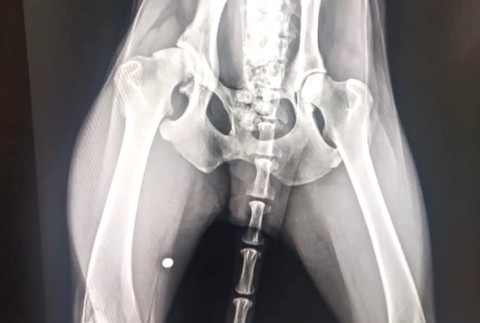

SPIŠSKÁ NOVÁ VES / Vyhladovaný na smrť, s brokom v tele a s vážne poranenou panvou. V takomto stave prijali týraného psíka pracovníci Slobody zvierat. Páchateľovi hrozí dvojročný pobyt za mrežami.

Psík sa stal terčom ľudskej krutosti. Okrem toho, že sa po ňom strieľalo, žil dlhodobo bez vody a jedla. Od veľkého hladu mal dokonca plný žalúdok nestrávených kostí. Jeho zdravotný stav bol doslova kritický.

Utýraný psík bol na tom tak zle, že ho museli ratovať veterinári. V bratislavskom útulku podstúpil sériu vyšetrení. "Bol v tak vážnom zdravotnom stave, že ani nebolo možné ho operovať. Sme museli čakať týždne na to, aby jeho stav bol natoľko stabilný, aby sme mohli riešiť aj zlomeninu jeho zadnej ľavej končatiny," opísala Devínska.

Problémy zúboženému psíkovi navyše spôsoboval aj starší brok, ktorý mu uviazol v tele, keď po ňom strieľali. "Nevieme na základe čoho sa stal Odin terčom takejto ľudskej zloby. Bol mu nájdený brok v pravej zadnej končatine," dodala Devínska.